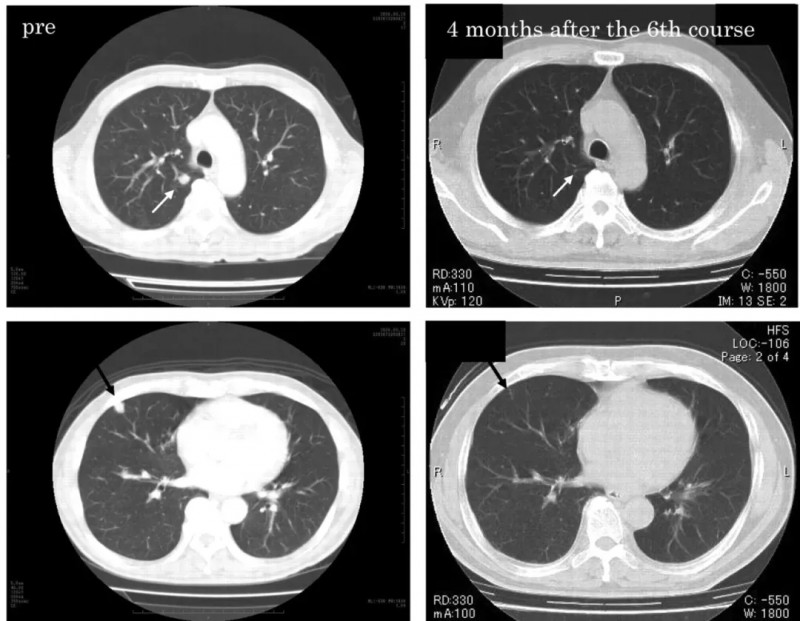

γδT细胞助肾癌患者肺部多个转移灶消失,2年无复发生存

《AnticancerResearch》曾报道一则经典案例:一名在根治术后出现肺部转移的肾细胞癌患者,在接受γδT细胞+IL-2+唑来膦酸联合治疗后,实现持续完全缓解。

该患者是一位61岁男性,确诊为右侧透明细胞型肾细胞癌(3级,pT1b分期),伴肺转移,先接受根治性肾切除术,术后给予干扰素α(IFN-α)治疗,但CT显示肿瘤负荷无明显变化。在IFN-α洗脱期一个月后,给予低剂量IL-2+唑来膦酸+自体体外活化的Vγ2Vδ2T细胞(γδT细胞的一种)联合治疗。

振奋的疗效随之显现:CT检查发现,治疗前的多发性肺转移灶,经3个疗程Vγ2Vδ2T细胞联合治疗后显著缓解,6个疗程后完全消失;患者在完成最后一个疗程后,已持续2年保持完全缓解(CR)状态(详见下图),且未接受任何针对肾细胞癌的额外治疗。

▼该患者治疗前、治疗第6个疗程后4个月的代表性CT图像

▲图源“anticancer research”,版权归原作者所有,如无意中侵犯了知识产权,请联系我们删除